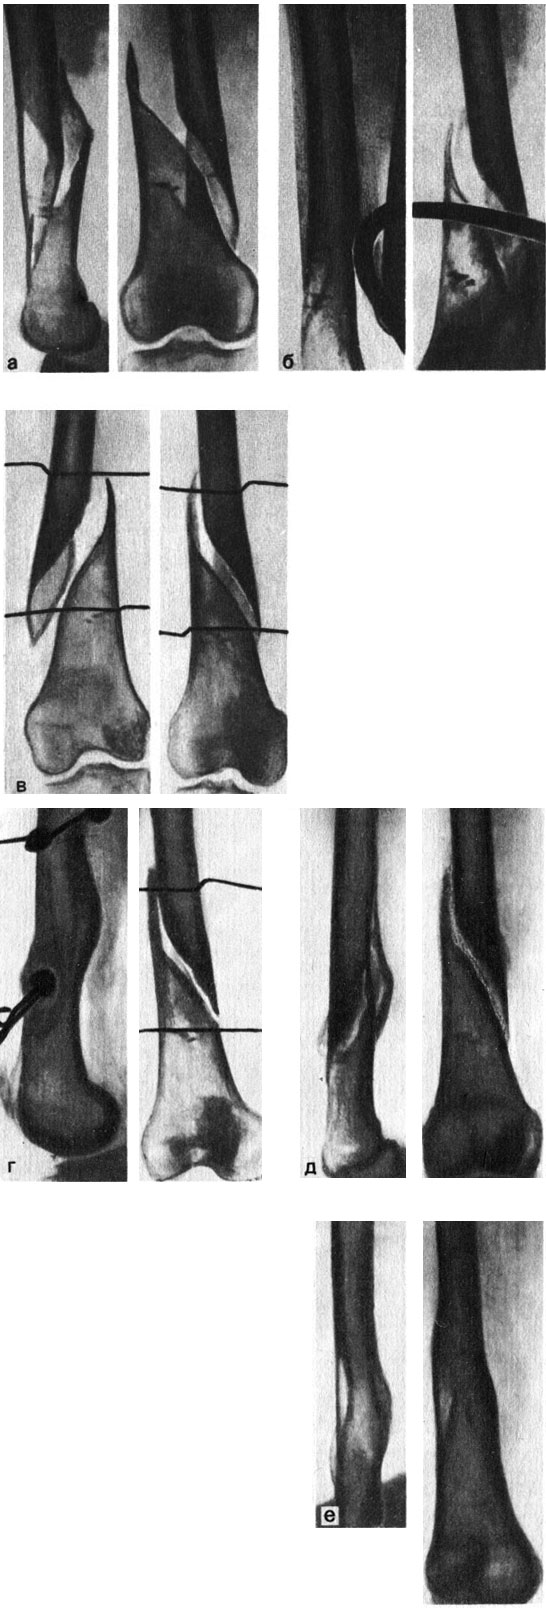

Рис. 109. Рентгенограммы правой бедренной кости больной С. а - после травмы; б - через месяц; в - наложено боковое скелетное вытяжение; г - отломки сопоставлены; д - после снятия вытяжения; е - результат лечения

Состояние больной стало удовлетворительным лишь через месяц. К этому времени на рентгенограмме была видна мозоль при сохранившемся смещении отломков. Наложено боковое постоянное демпферированное скелетное вытяжение (рис. 109), груз по 8 кг на каждую спицу. Достигнуто почти полное сопоставление отломков. Через 6 нед вытяжение снято. Выписана без гипсовой повязки.

Осмотрена через 2 года: нога не болит, движения в коленном суставе не ограничены, хромоты нет. На рентгенограммах виден сросшийся перелом бедра, мозоль небольшая, ось бедра правильная. Оценка по таблице Улицкого - 30 баллов - отлично.

Наблюдение иллюстрирует возможность моделирования первичной мозоли при несвежем переломе бедра у 70-летней больной постоянным демпферированием боковым скелетным вытяжением большими грузами. Перелом сросся малой мозолью. Таким образом, постоянное боковое скелетное вытяжение оказалось в этом случае еще и моделирующим скелетным вытяжением.